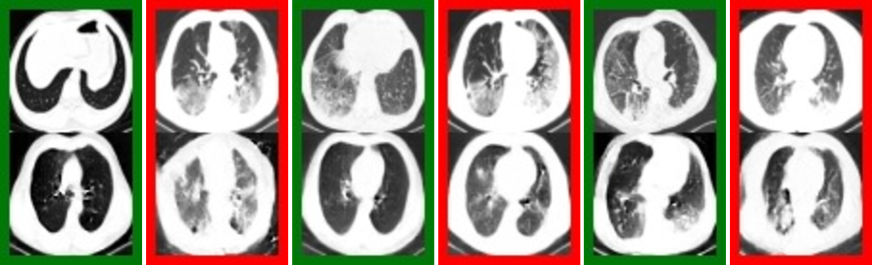

The original samples along with the synthetic samples generated by preserving original conditional feature representation and a different local noise for CT scans are shown in Fig. 5. The characteristic features for COVID CT scan samples, i.e., ground-glass opacity are well preserved in the synthetic samples. At the same time, the non-conditional local features, e.g. axial plane position for CT scans are considered as local noise. Since original samples for normal and pneumonia cases are merged together to form a single Non-COVID class, sometimes the corresponding synthetic image for a normal sample is a sample with pneumonia characteristics and vice-versa. This occurs since the conditional model learns to treat them as local information. The ability to decouple the feature representations for given conditions from other information in the data, as exhibited by our model, should be considered the strength of an effective conditional generative model.